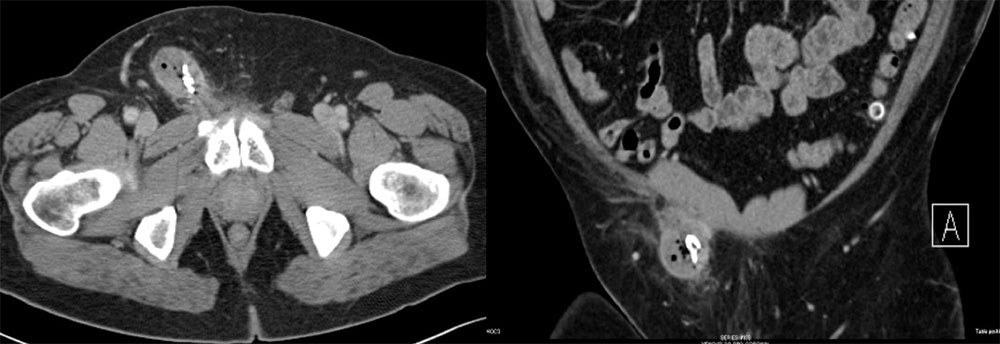

Case 11  55-year-old man with a pancreatic mass and history of recent inguinal hernia repair. Axial (A) and coronal MPR (B) CT images of the pelvis reveal:

Case 11  55-year-old man with a pancreatic mass and history of recent inguinal hernia repair. Axial (A) and coronal MPR (B) CT images of the pelvis reveal:

Retained Surgical Sponge

Retained Surgical Sponge  This is another example of how the sponge marker is better displayed with 3D volume rendering |